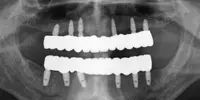

Implant tedavisi